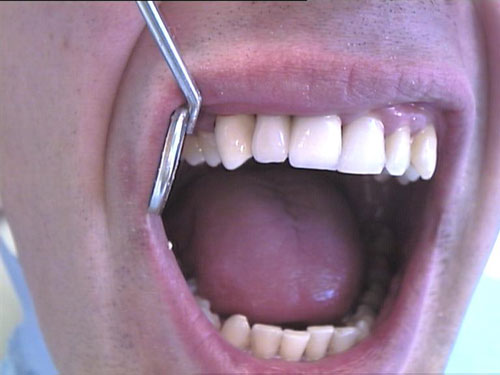

Keramikkrone 1

Keramikkrone 2